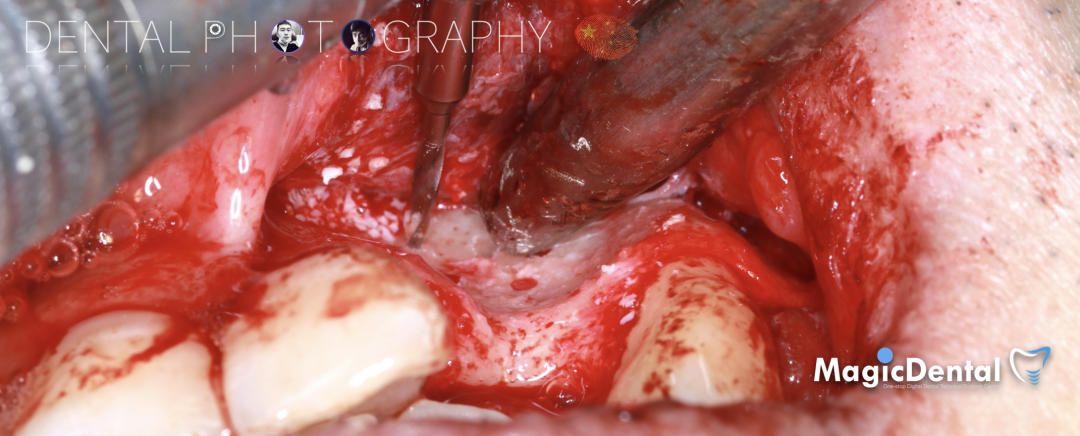

骨膜减张,放置骨粉,放置骨块,钛钉固定骨块。

固定骨片,修整骨块边缘,继续放置骨粉覆盖骨块及受植区,放置骨膜,严密缝合创口。